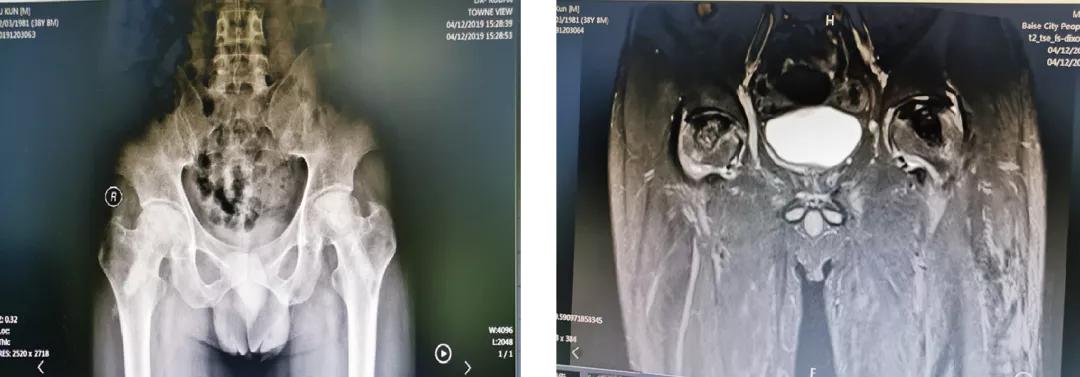

云南的苏先生今年38岁,出现双侧髋关节疼痛、活动受限1年多,被 明确 诊断为“双侧股骨头坏死”,坏死处于ARCO分期3期。在当地医院使用多种办法治疗,无明显效果,而后转到百色市人民医院关节与运动医学科。在患者及其家属强烈的保髋愿望下,科室选择了骨科机器人辅助下的微创保髋治疗,术后效果良好,患者满意。

术前辅助检查